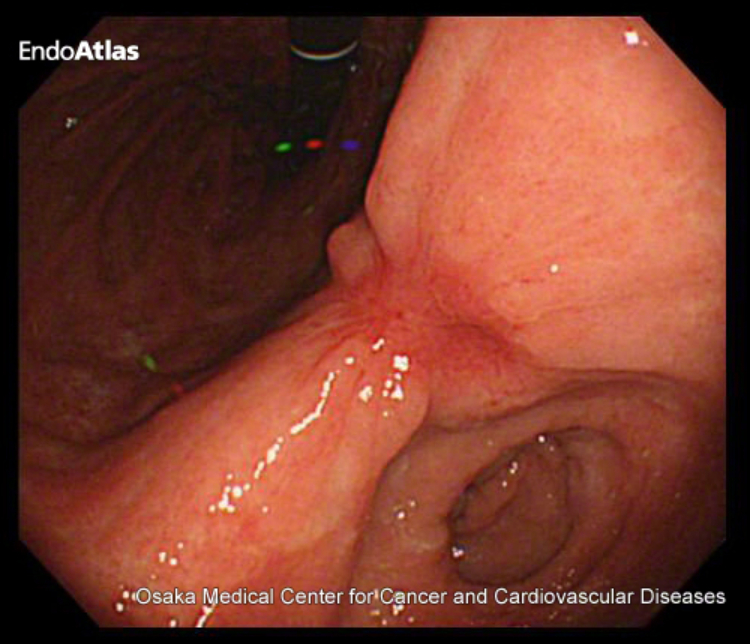

胃内視鏡検査(胃カメラ)

内視鏡で胃の内部を直接観察し、疑わしい病変があれば組織を採取(生検)し、病理診断を行います。

早期発見に最も有効な検査です。

内視鏡治療(EMR・ESD)

がんが粘膜層にとどまる早期の段階で行われる治療法です。

内視鏡を使ってがん組織を切除するため、体への負担が少なく、入院期間も比較的短く済みます。